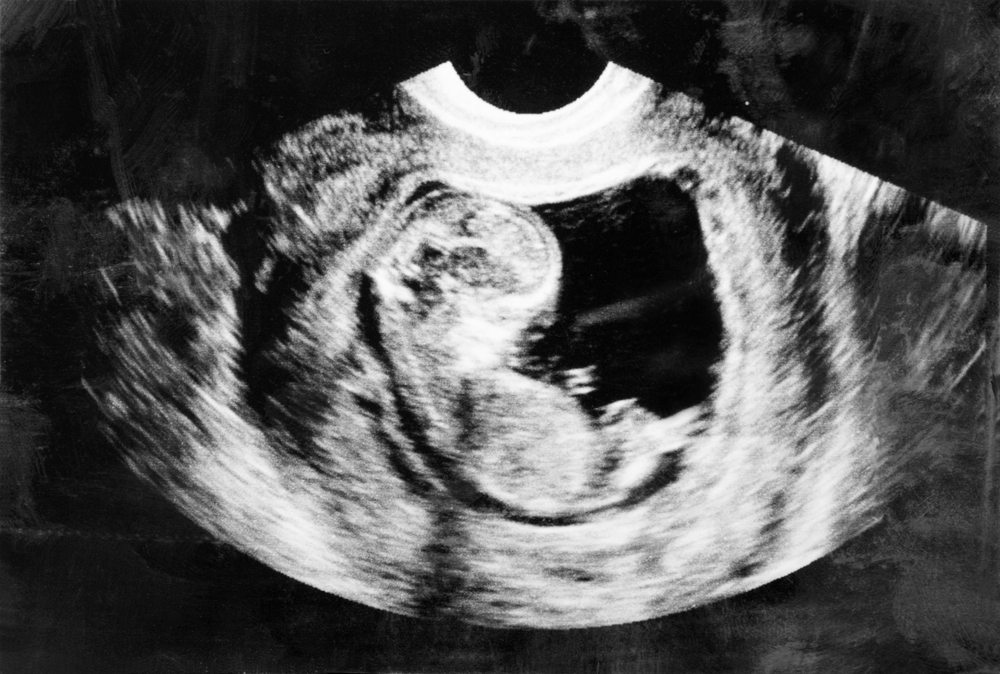

Normally, IVF involves uniting a woman’s egg with a man’s sperm to create a tiny embryo that is implanted into the mother. But this straightforward technique is not possible for women who suffer from a mitochondrial disease.

If a healthy woman donates her egg, scientists can remove its nucleus (which contains most of the cell’s DNA) and replace it with the nucleus extracted from the mother’s egg. The resulting egg contains nuclear DNA from the mother and healthy mitochondria from the donor – i.e., the “third parent.” The new egg can then be fertilized and implanted into the mother.